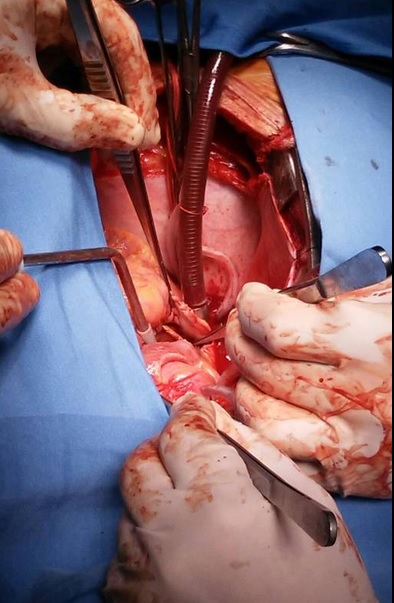

BUENOS AIRES. Médicos de un hospital en Argentina extrajeron del corazón de un hombre, de 42 años, un palillo de dientes que había ingerido por accidente y que fue descubierto cuando lo operaban por una infección cardiaca que padecía desde hacía unos seis meses, informaron hoy a Efe fuentes médicas.

“Llegó al hospital con mucha fiebre y con una infección originada en el corazón”, dijo a Efe el doctor Fernando Cichero, jefe de cirugía cardiovascular del Hospital Fernández.

Durante la intervención quirúrgica, se le extrajo “para sorpresa de todos, un palillo de madera completo del corazón”, remarcó.